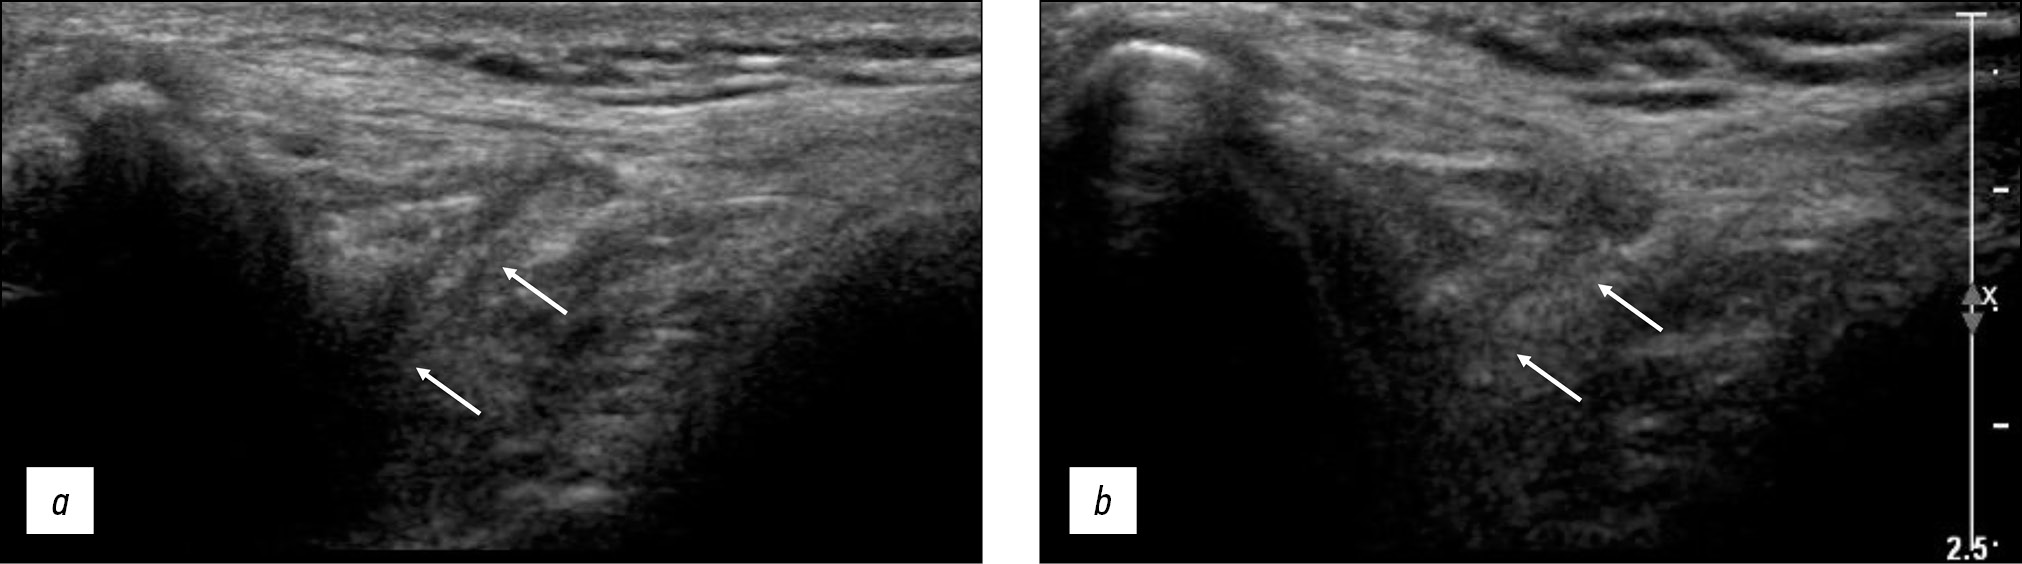

После правильного расположения датчика, проводилась статическая оценка тканей вокруг медиальной границы надколенника (рис. 5). В этой проекции (рис. 5б) наличие МПСС определялось как непрерывная полосо-образная эхоструктура, расположенная непосредственно на передней поверхности медиального мыщелка бедренной кости. Его необходимо было отличать от другой анатомической структуры в этой области, а именно крыловидной складки, которая представляла собой синовиальную складку, появлявшуюся при расслабленном состоянии коленного сустава [21]. Эхосигнал крыловидной складки имел треугольную форму и визуализировался как структура повышенной эхогенности по сравнению с эхогенностью складки и локализовался непосредственно под медиальной поддерживающей связки надколенника.

Рис. 5. Сонограммы коленного сустава: a — сонограмма при расположении датчика в рентгенологическом положении 1, более проксимально; b — сонограмма при расположении датчика в рентгенологическом положении 2, правильно; c — сонограмма при расположении датчика в рентгенологическом положении 3, более дистально. Стрелками обозначена медиопателлярная синовиальная складка

Fig. 5. Knee joint sonograms: a — sonogram when the sensor is located in the X-ray position 1, more proximally; b — sonogram when the sensor is located in the X-ray position 2, correct; c — sonogram when the sensor is located in X-ray position 3, more distally. Arrows indicate the mediopatellar synovial fold

Если ультразвуковой датчик располагался слишком проксимально, то определялось ультразвуковое изображение медиальной головки четырехглавой мышцы над медиальным мыщелком бедренной кости (рис. 5а). Если датчик располагался слишком дистально по отношению медиальному мыщелку бедренной кости, его изображение становилось вогнутым, неправильным с невозможностью визуализации расположения надколенника (рис. 5в).